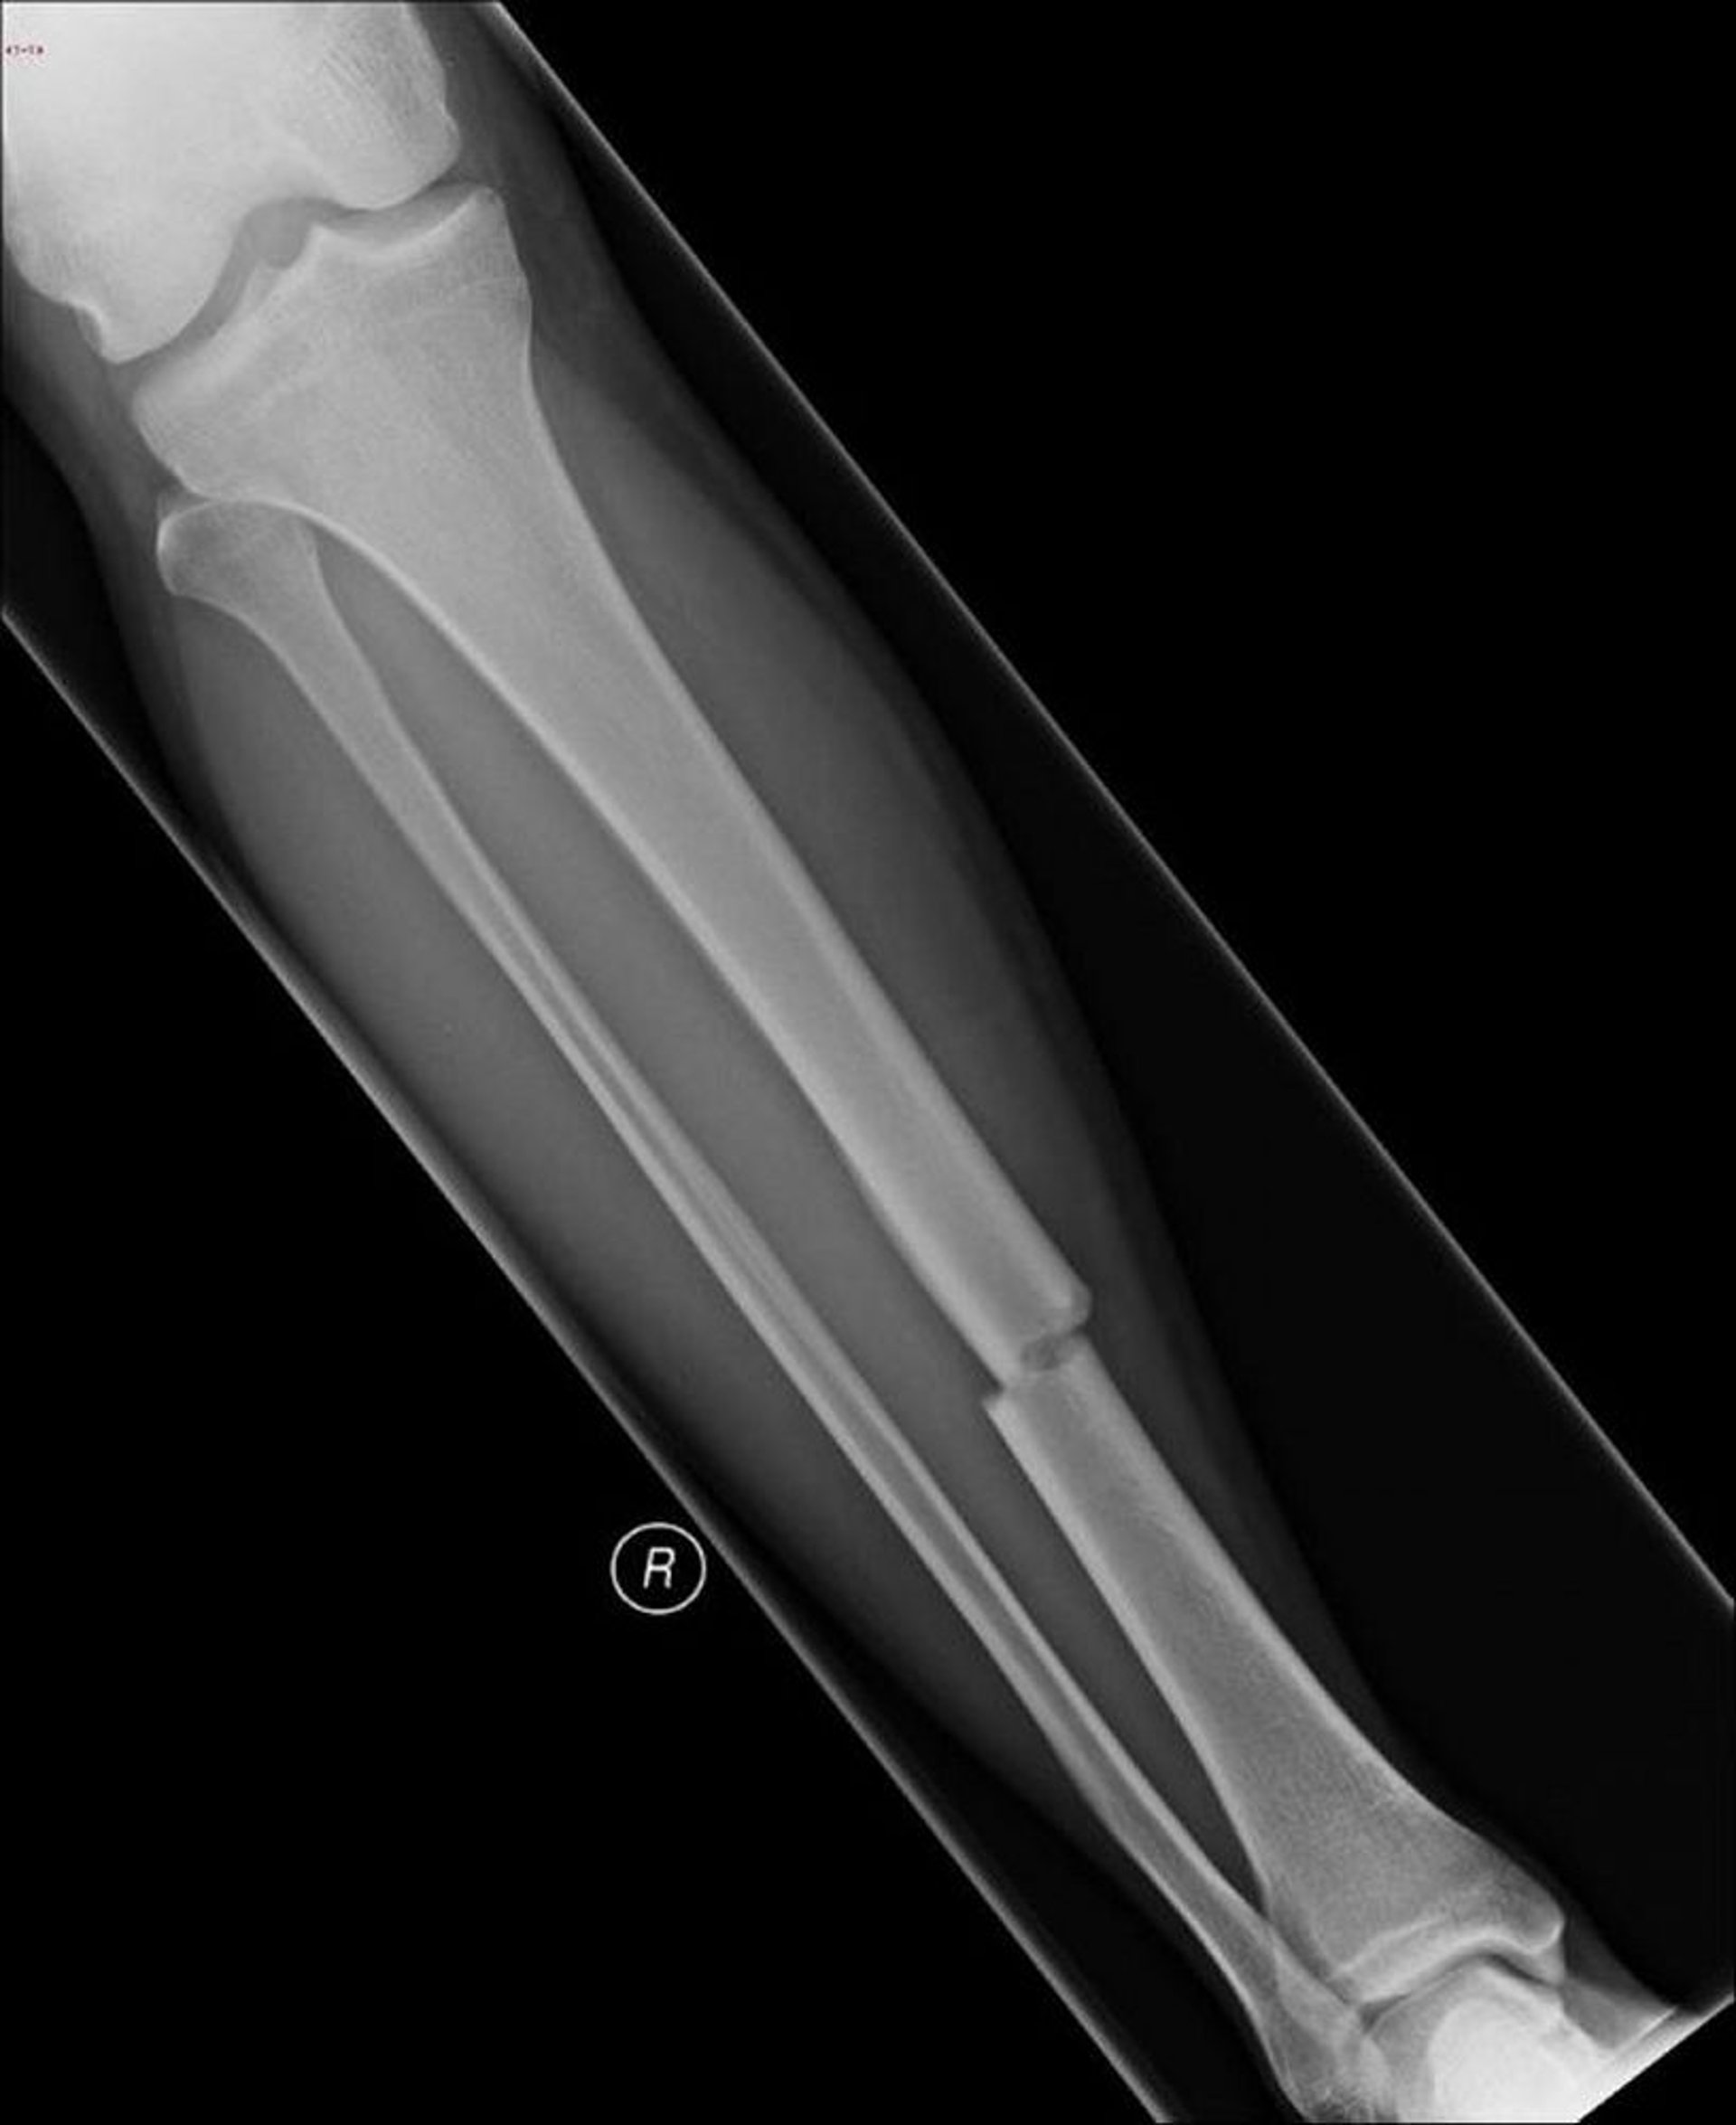

Поперечный перелом диафиза большеберцовой кости

При этом поперечном переломе поражается средняя часть голени.

Image courtesy of Danielle Campagne, MD.